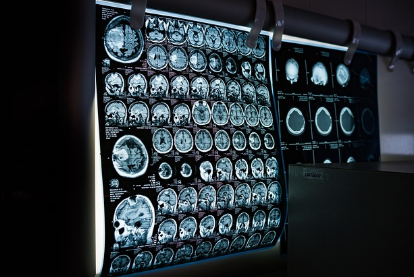

바쁜 일상 속에서 놓치기 쉬운 건강, 정기적인 건강검진을 통해 미리 질병을 예방하고 건강을 유지하는 것이 중요합니다. 하지만 건강검진 대상자 조회, 병원 선택, 검사 전 준비 등 궁금한 점이 많으실 텐데요. 이번 글에서는 건강검진에 대한 모든 것을 상세히 알려드려 건강검진을 성공적으로 마칠 수 있도록 돕겠습니다.

국가에서 국민의 건강 증진을 위해 시행하는 무료 또는 저렴한 비용의 건강검진입니다. 만성질환 예방을 위한 생활습관 개선과 조기 암 진단을 목적으로 하며, 대상자와 검사 항목은 나이와 성별에 따라 달라집니다.